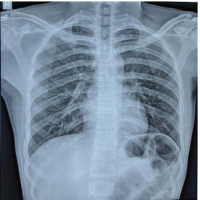

A 52-year-old male came to the hospital with an alleged history of a slip and fall from a motorcycle and sustained injury to his chest and bilateral shoulder. A history of pain and swelling over the bilateral shoulder was present, which was sudden in onset, aggravated on movement, and relieved on rest. He also gives a history of pain in the right chest. No history of loss of consciousness, Seizures, vomiting, and ENT bleeding. On examination of his bilateral shoulders, there was swelling present, he had tenderness in the lateral end of the clavicle, his shoulder range of movements was significantly restricted due to pain, and there were no neurovascular deficits. His chest compression test was positive on the right side. Plain radiographs of his chest with bilateral shoulders were taken, which showed an undisplaced right lateral end of clavicle fracture, comminuted fracture of the left lateral end of clavicle with fracture of right 4th, 5th, 6th, and 7th rib (Fig. 1a). Computed tomography of the chest showed comminuted extra-articular minimally displaced fracture seen involving the mid and lateral third of the left clavicle with adjacent soft-tissue inflammatory changes. A complete transverse fracture involving the lateral one-third of the right clavicle, with mild inferior displacement of the distal fragment (Fig. 1b). The right acromioclavicular joint (ACJ) appears normal. Comminuted displaced fracture of the posterior shaft of the right 4th, 5th, 6th, and 7th rib.